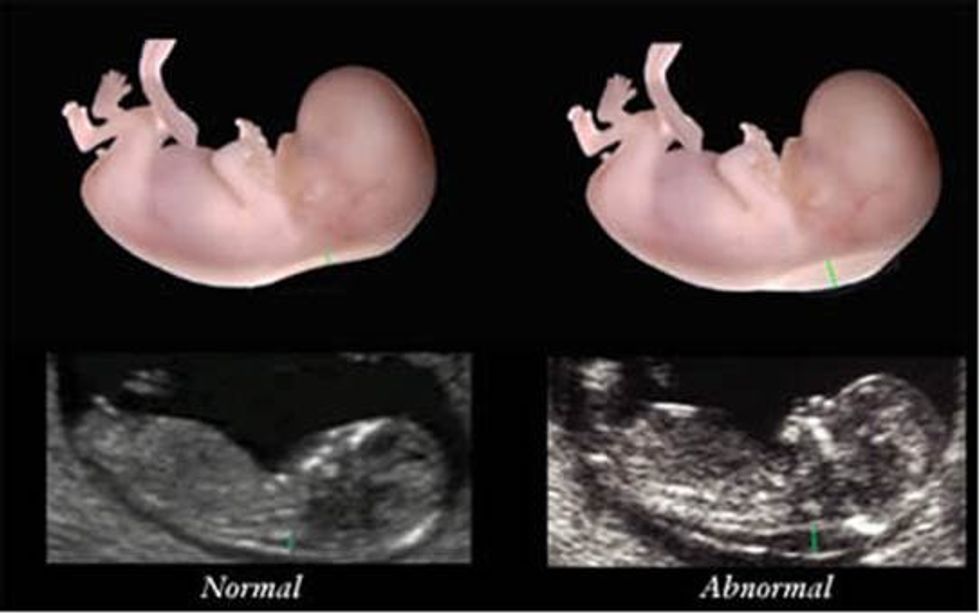

• Ekzaminimin ultrasonografik për të matur pjesën e pasme të qafës së bebes e cila quhet translucenca nuhale (nuchal translucency-NT) DHE